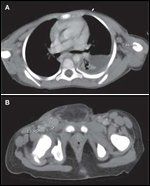

FIGURE

Anaplastic large cell lymphoma.

In this patient, computed tomography (CT) of the chest

(A)

demonstrates a left pleural effusion and bilateral axillary lymphadenopathy measuring up to 7.6 cm. CT of the pelvis

(B)

demonstrates inguinal lymphadenopathy measuring up to 2.4 × 1.4 × 2 cm at the right groin.

On the third hospital day, the patient was noted to have new supraclavicular, cervical, and axillary lymphadenopathy. Concern for an oncological process prompted computed tomography (CT) imaging of the head, neck, chest, abdomen, and pelvis; the scan revealed a large left pleural effusion and left cervical, left supraclavicular, bilateral axillary, diffuse abdominal, and bilateral inguinal lymphadenopathy (Figure). On gallium scanning, the abnormal regions on the CT scan were gallium avid. Bilateral bone marrow aspirates and biopsies were negative for malignancy. Examination of the pleural fluid did not demonstrate any malignant cells. Her cerebrospinal fluid (CSF) was acellular, and cytology evaluation did not reveal any malignant cells. Results of a subsequent biopsy of the right inguinal lymph node were diagnostic of anaplastic large cell lymphoma (ALCL), lymphohistiocytic variant. This patient’s ALCL was anaplastic lymphoma kinase (ALK)–positive on immunohistochemical staining. However, neither cytogenetics nor fluorescence in situ hybridization demonstrated any translocations involving chromosome 2 (the location of the ALK gene) that might have accounted for the expression of the ALK protein.